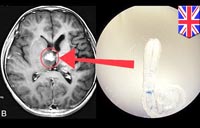

Bệnh ký sinh trùng sán nhái (Sparganosis) là nhiễm sán loại Diphyllobothrium hay ấu trùng plerocercoid larvae của giống Spirometra gồm có các loài như S. mansoni, S. ranarum, S. mansonoides và S. erinacei. Lần đầu tiên được mô tả ở Trung Quốc bởi Patrick Manson vào năm 1882 và ca bệnh đầu tiên ở người được báo cáo bởi tác giả Charles Wardell Stiles từ Florida, Mỹ vào năm 1908.

Một khi con người nhiễm, ấu trùng kết nang vô tính (plerocercoid larvae) di chuyển trong vị trí dưới da, ở đó chúng thường phát triển thành các nốt cục đau. Sự di chuyển của ấu trùng vào trong não dẫn đến bệnh sán nhái ở não (cerebral sparganosis), nếu di chuyển đến mắt dẫn đến bệnh sán nhái ở mắt (ocular sparganosis). Bệnh sán nhái lưu hành nhiều nhất ở Đông Á, mặc dù số ca đã được mô tả tại các quốc gia trên khắp thế giới, khoảng 300 ca được mô tả trên y văn đến cuối năm 2003 và hiện nay nhiều nước đã tổng hợp trong 15 năm qua con số cũng lên đến gần 1000 ca đến năm 2018. Chẩn đoán thường không đặt ra mãi đến khi ấu trùng sán nhái (sparganum larva) được phẩu tích lấy ra xác định. Praziquantel là thuốc được lựa chọn để điều trị sán nhái, mặc dù hiệu quả của thuốc vẫn chưa biết đầy đủ và phẩu thuật loại bỏ sán ra khỏi tổn thương nhìn chung là phương pháp điều trị tốt nhất. Các can thiệp y tế công cộng nên tập trung vào vệ sinh nguồn nước và thực phẩm, cũng như giáo dục sức khỏe về về bệnh tại các vùng nông thôn thường sử dụng nhái làm thuốc đắp (poultices).